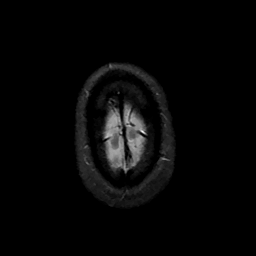

MR Study #11, May 5, 1991 -- Slice #47

[Home][Help][Clinical][Tour 1][Tour 2] Slice 47